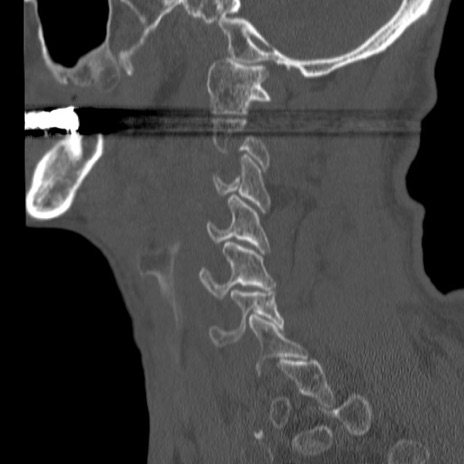

症例46 頚椎CT(矢状断像)

【症例】80歳代男性

【主訴】両側頚部〜上肢のしびれ

【現病歴】昨日、自宅内で転倒、その後より上記症状あり。意識障害なし。

【身体所見】両側上肢のallodynia(熱痛覚過敏)あり。MMTおよびDTRは正確な所見取れず。両上肢の挙上はなんとか可能。

異常所見と診断は?